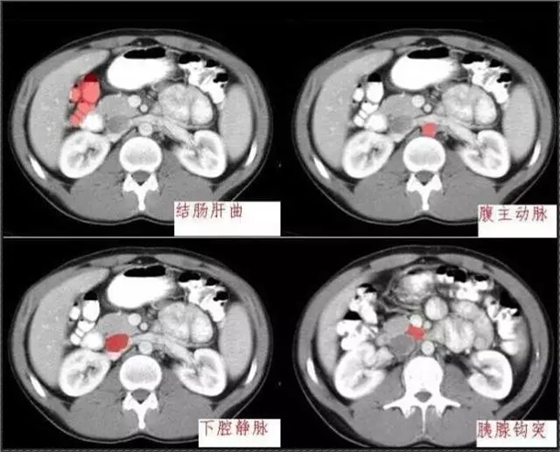

640.webp.jpg

640.webp (1).jpg